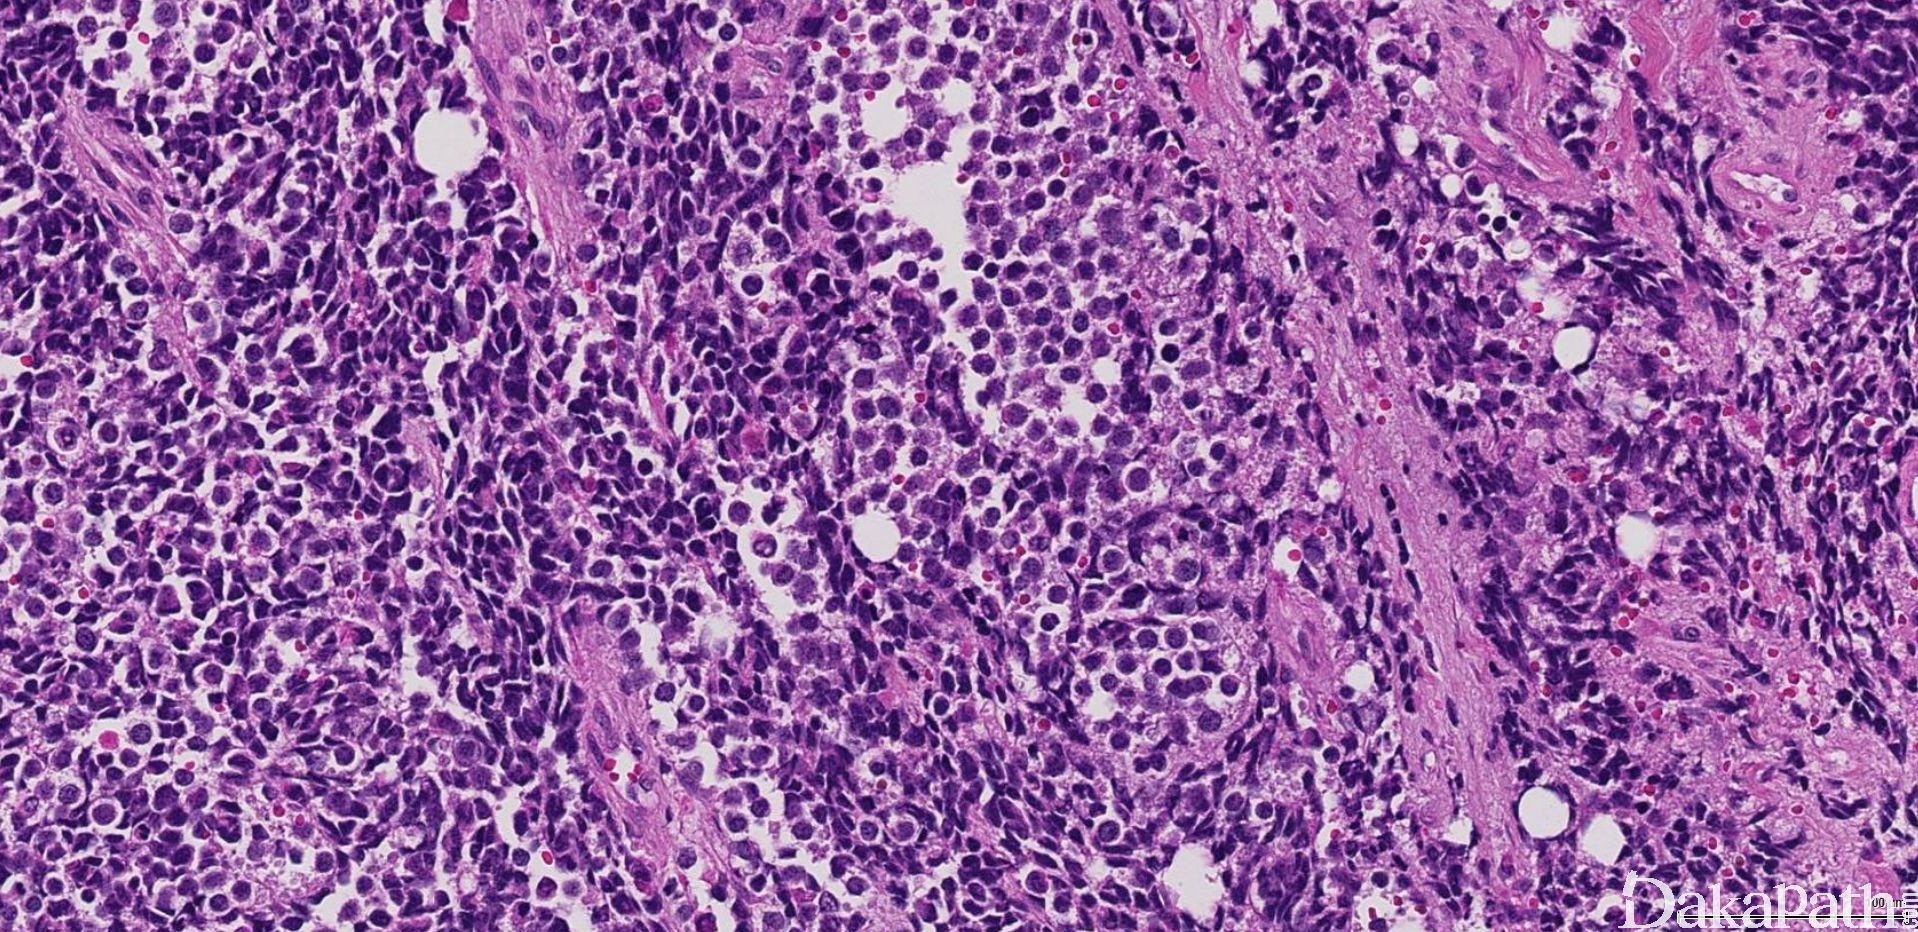

3. 经典型:

4. 瘤细胞排列成片状和巢状而贴附于纤维性间隔上,巢中央瘤细胞黏附性差,相互解离,形成特征性的假腺泡状或微囊状结构;

5. 肿瘤由未分化的原始间叶性细胞及少量早期分化的幼稚横纹肌母细胞组成;

6. 原始间叶性细胞呈圆形、卵圆形或小多边形,胞质少,核深染,核分裂像易见;

7. 腺泡中央的横纹肌母细胞多呈圆形或卵圆形,有时可见到胞质内横纹;

8. 部分病例可见散在的胞质淡染或弱嗜酸性,核位于胞质周边的多核巨细胞;